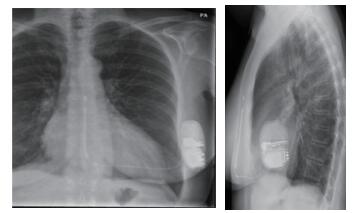

患者女性,56岁,因长QT综合征植入S-ICD 1.5年。既往因“心脏瓣膜病”于2016年4月19日行二尖瓣、三尖瓣位机械瓣膜置换术,术后常规抗凝,维持INR值为2~3。术后6个月由于长QT综合征导致的反复室颤,考虑到经静脉植入ICD卡瓣等问题,选择植入S-ICD,常规S-ICD ECG筛选通过后,于2016年11月29日植入一台S-ICD(图 1)。术后继续华法林抗凝治疗,患者在2018年5月28日07:41睡觉的过程中接受到了两次电击,遂来医院就诊,复查电解质未见异常; 心电图无室性心动过速和室早事件; 患者电击前无明显不适症状,放电后亦无栓塞表现。联系ICD厂家工程师,于当日20:42使用S-ICD程控仪对患者植入的S-ICD进行问询,测试电池、阻抗都在正常范围内(阻抗55 Ω, 直接测量所得)。设备记录到了两次事件(图 2),分析两次放电事件的EGM,S-ICD感知向量为出院前自动优化的Primary向量(增益为1),这个向量所记录到R波幅值较低(图 3)。当发生短阵的房颤事件,f波都被误感知为R波,因为频率较快,标记为“T”(快室性心律失常事件),满足18/24诊断标准后开始充电,充电后确认快心室率事件仍然存在后放电,放电终止了房颤。

图 1 患者植入S-ICD后胸片